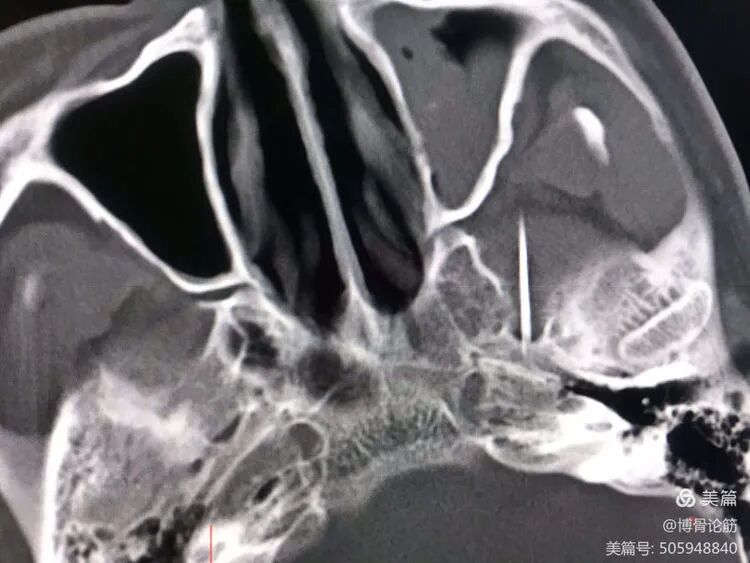

术中CT成像三维立体重建

在CT手术室,陈元振主任团队为患者实施了介入微创手术——三叉神经半月节双极脉冲射频调节术。患者取水平仰卧位,颈部轻度伸展,头轻度后仰。CT定位三维重建显露左侧卵圆孔,CT引导下取导管针沿预定方向进行穿刺,针尖到卵圆孔,CT监视下调整针方向及深度,置入射频针芯,予以脉冲射频,行脉冲射频2周期,射频完毕,退针,外敷创口。